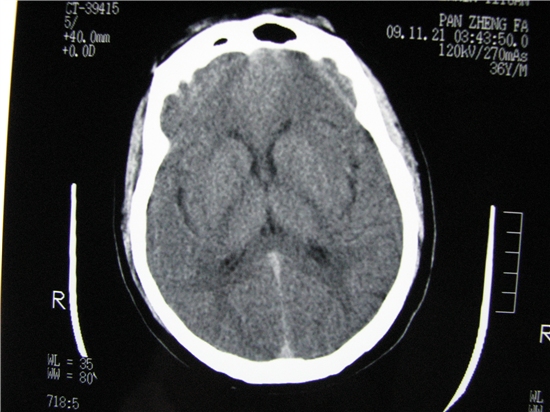

标题: CT23231:男 32岁 车祸伤,鼻腔内出血明显。 [打印本页]

标题: CT23231:男 32岁 车祸伤,鼻腔内出血明显。

额窦内及额部软组织内可见多发游离类骨质密度影,考虑额骨骨折可能。

鼻骨层面较少,无法判断鼻骨。

建议薄扫一下。

左侧额骨、鼻骨骨折,头面部软组织肿胀。

左侧额骨、鼻骨骨折,额窦内的应该是游离骨块